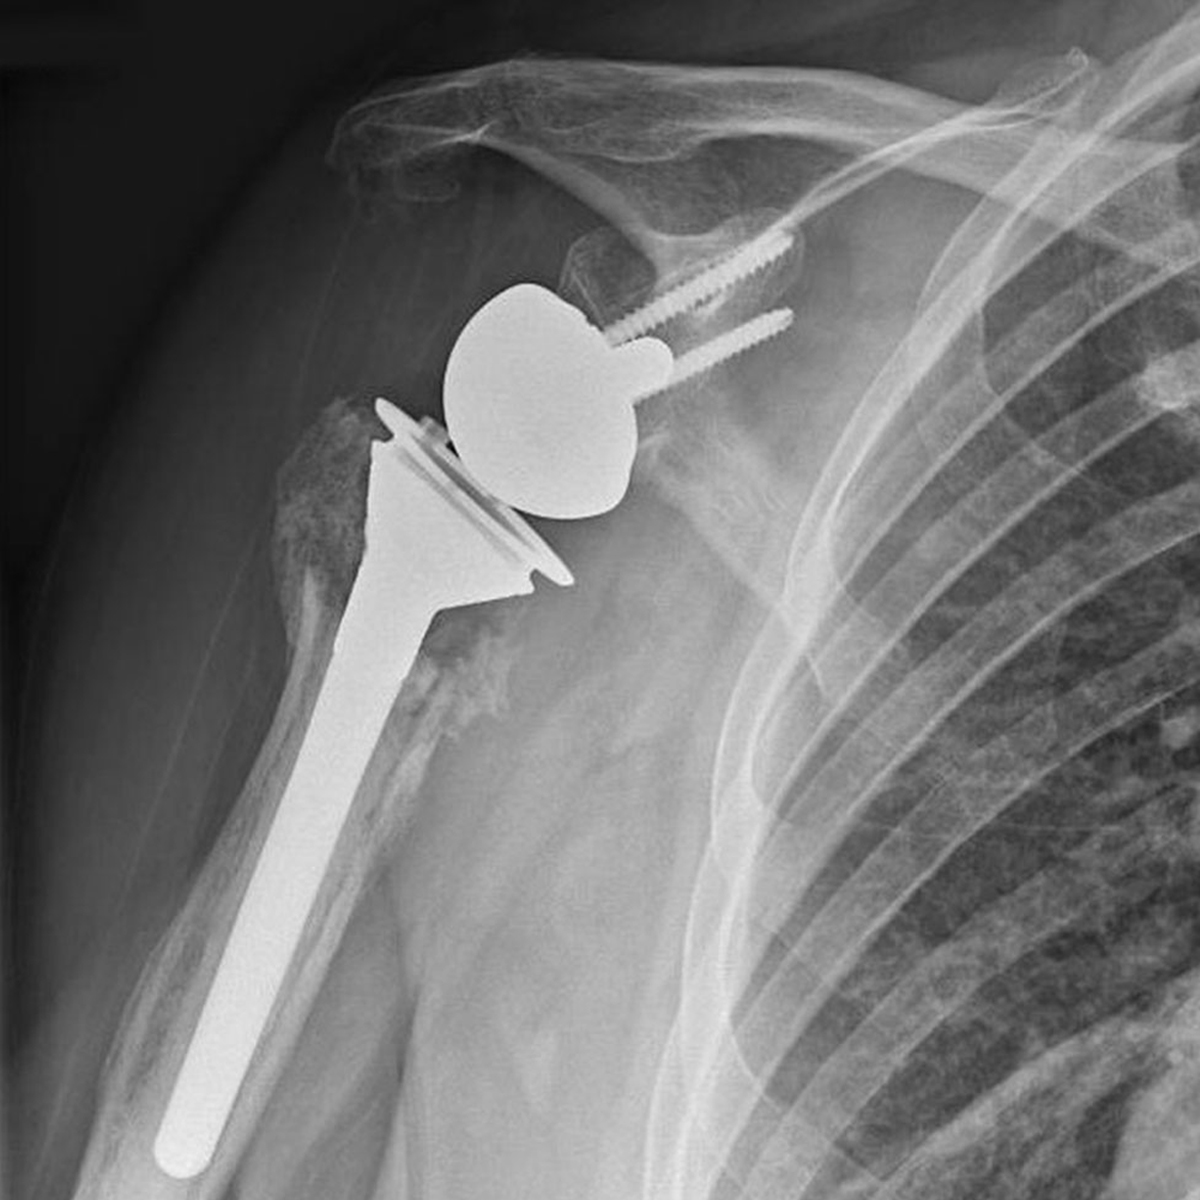

• Reverse Total Shoulder Replacement

Reverse total shoulder replacement is used for people who have:

• Completely torn rotator cuffs with severe arm weakness

• Severe arthritis due to rotator cuff tearing

• Had a previous shoulder replacement that failed

In reverse total shoulder replacement, the socket and metal ball are interchanged A metal ball is attached to the shoulder bone(glenoid), and a plastic socket is attached to the upper arm bone(humerus). This allows the patient have a better shoulder movements.